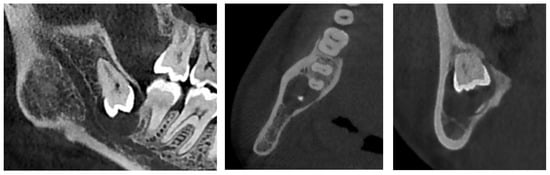

Figure 2.

CBCT X-ray of case #1.

There was also no periosteal reaction, pathological fracture, evident signs of sequestration or sclerosis of the surrounding bone, nor infiltration of the perimandibular soft tissues. Tooth #38 had two roots, and the mesial root came into contact with the lingual wall of the IAC. The radiological appearance evoked a DC. Differential diagnoses included odontogenic keratocyst and unicystic ameloblastoma. The lesion was enucleated in toto together with tooth #38 under local anesthesia. The diagnosis of DC was confirmed by histopathological examination (Figure 3). The patient was followed for four years. At 12 months follow-up, OPG showed satisfactory healing of the enucleation cavity and tooth #37 was still vital (Figure 4). The patient was followed-up for 4 years with no signs of recurrence.